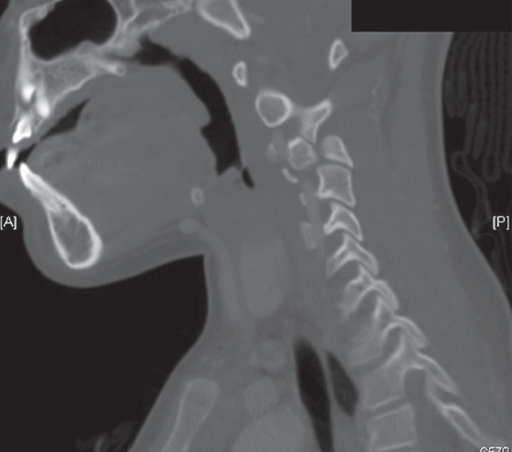

Figure 1 – This sagittal image demonstrates a jumped facet at C3 and

a kink in the vertebral artery.

The next day the patient’s CT scan was evaluated by the attending radiologist, who found a right C3-4 facet dislocation. The child was called back to the ED for reevaluation. A neck CT scan with contrast demonstrated a jumped facet at C3, and a kink in the vertebral artery (Figure 1) and normal alignment of the left side (Figure 2).